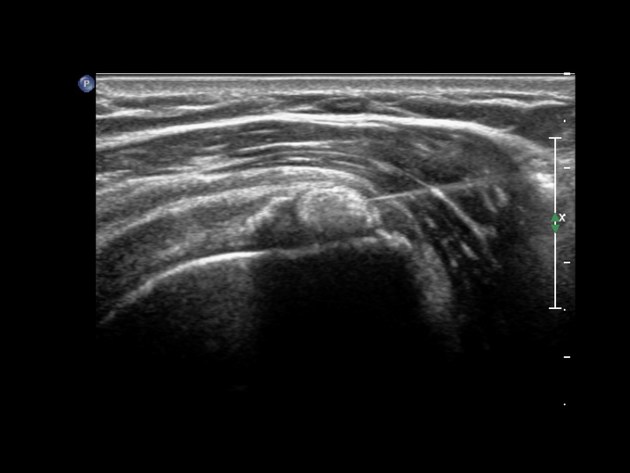

Siêu âm MSK (Ưu tiên)

• Đánh giá động (real-time)

• Phân loại hình thái vôi (A–D)

• Phát hiện bursitis, rách gân kèm theo

• Hướng dẫn thủ thuật can thiệp

• Doppler: đánh giá pha viêm

🖼 Hình 5 – Hình ảnh siêu âm gân trên gai

Trái: trục ngắn – tăng âm với bóng âm sau. Phải: trục dài – ổ vôi trong gân supraspinatus

Hình ảnh siêu âm gân trên gai